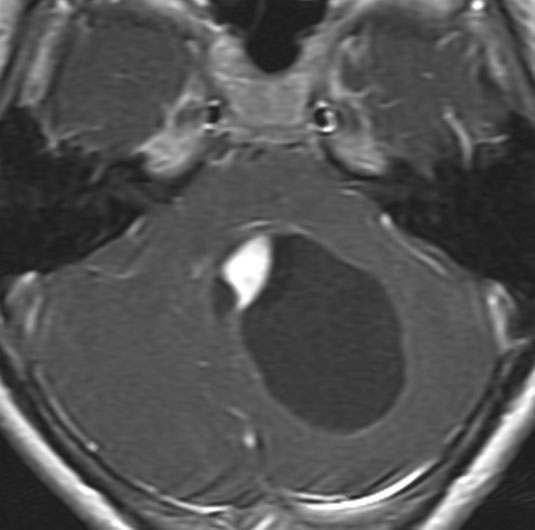

MR画像の特徴について(T2で白い)

pilocerebel-2pilocerebel-1pilocerebel-3

7歳の子の小脳虫部腫瘍です。左と中央のMRIをみると一見,髄芽腫に見えます。でもこれは毛様細胞性星細胞腫で,手術で全部取れて,後遺症もなく治りました(右側)。inverted T2(左側のCISS)では黒く(低信号)に写って小脳との境界が明瞭です。

T1強調画像のガドリニウム増強(左)ではわかりませんが,右のT2強調画像で腫瘍部分がとても白く(強い高信号)に写っているのが,最大の特徴です。多くの場合,T2強調画像で毛様細胞性星細胞腫の診断がつきます。このようなT2でかなり強い高信号になるものは毛様粘液性星細胞腫の成分を含むことが多いです。